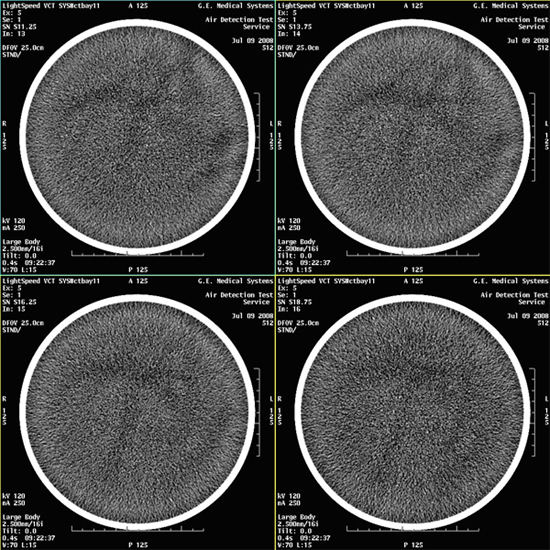

- Select VIEWER and review all images for

blotchy artifacts. (See Figure 1, Figure 2, and Figure 3). If an artifact is encountered, perform Tube Oil Cooling System Air Removal.note:

If air artifact exists, the air activity may be more significant in Images 13 through 16, 29 through 32, 45 through 48, and 61 through 64.

Figure 2. Images with Marginal Air Artifacts